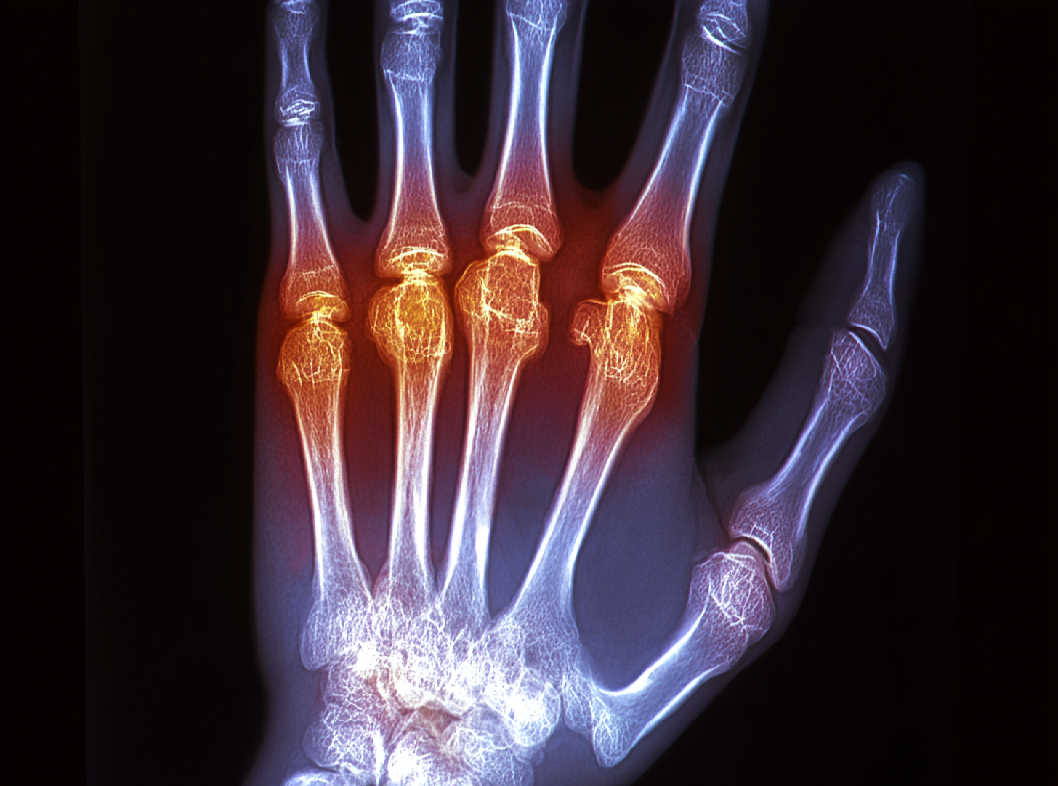

Боль в запястье. Пациенты могут испытывать боли, которые могут быть тупыми или острыми и усиливаться при движении сустава. Отек и воспаление. Возможно развитие отека (набухания) и воспаления в области полулунной кости, что также может сопровождаться краснотой кожи.

Рентгенография. Рентгеновские снимки позволяют врачам визуализировать структуру костей и выявить изменения в полулунной кости. В ранних стадиях заболевания изменения могут быть не так заметны.